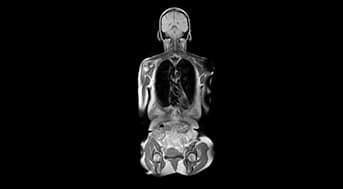

Cent combines full-body MRI, CT Calcium Scoring, DEXA, and 100+ blood biomarkers to detect diseases early - revelaing what blood tests often miss.

Full-Body MRI

Scans your entire body for cancers and structural issues.Detects problems early without any radiation.

DEXA

Measures bone density and body composition. Helps assess bone health, muscle mass, and metabolic risk.